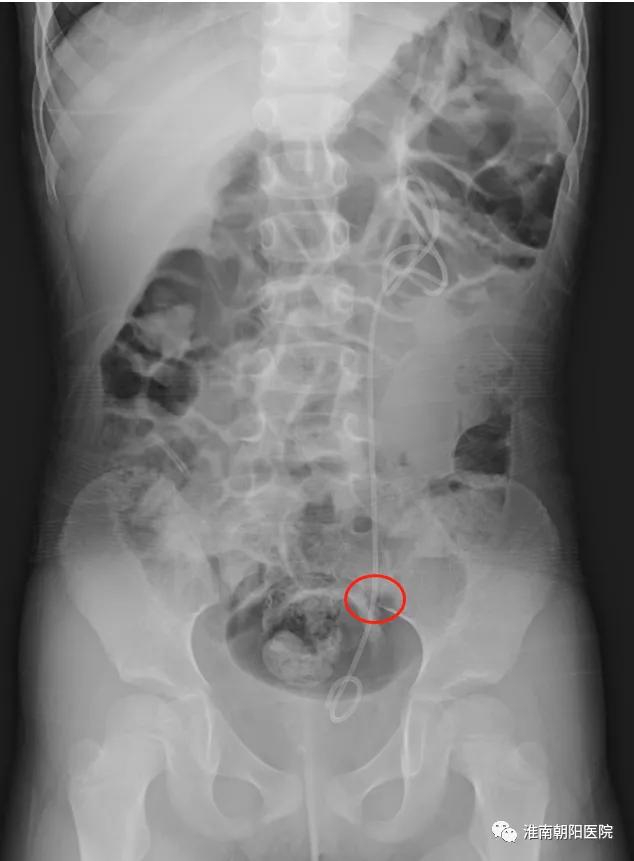

不久前,一位 4 岁小朋友患有输尿管结石,家人本来打算去上海治疗,后来听说淮南朝阳医院泌尿外科的微创技术,于是住院治疗。入院后患儿体温最高 39℃,在完善术前检查和抗感染治疗稳定的基础上,邓大溢副院长坐镇指导,方强副主任医师娴熟的应用输尿管镜钬激光碎石技术顺利粉末化结石,解除了梗阻,患儿顺利出院。

术前情况